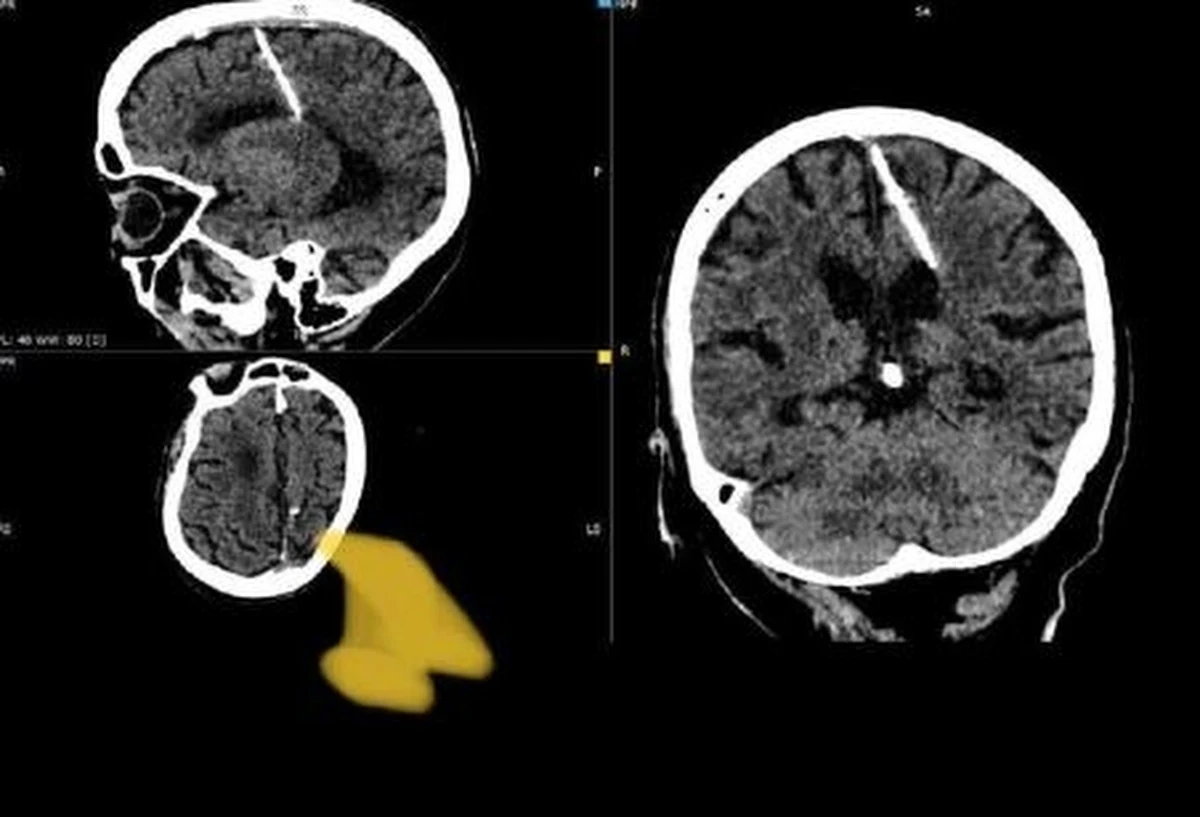

Starsza kobieta z dalekiego wschodu Rosji przeżyła 80 lat z 3-centymetrową igłą w mózgu. Odkryli to przypadkiem lekarze, którzy badali ją za pomocą tomografii komputerowej - poinformował „The Guardian”, powołujący się na lokalne władze medyczne.

"Igła wbiła się w lewy płat ciemieniowy, ale mimo to dziewczynka przeżyła" - poinformował miejscowy wydział sanitarny, dodając, że pacjentka nigdy nie skarżyła się na żadne dolegliwości, które mogłyby być skutkami igły w mózgu.

Lekarze stwierdzili, że nie będą podejmować prób usunięcia igły w obawie przed pogorszeniem jej stanu.